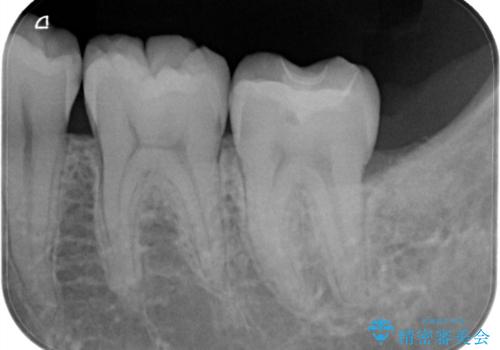

- 検査の結果、虫歯が見つかった患者様です。

白く目立たないものでの治療をご希望されたため、セラミックインレーでの治療となりました。

適合の良いセラミックインレーで修復することで見た目の綺麗さを保ったまま治療することができます。